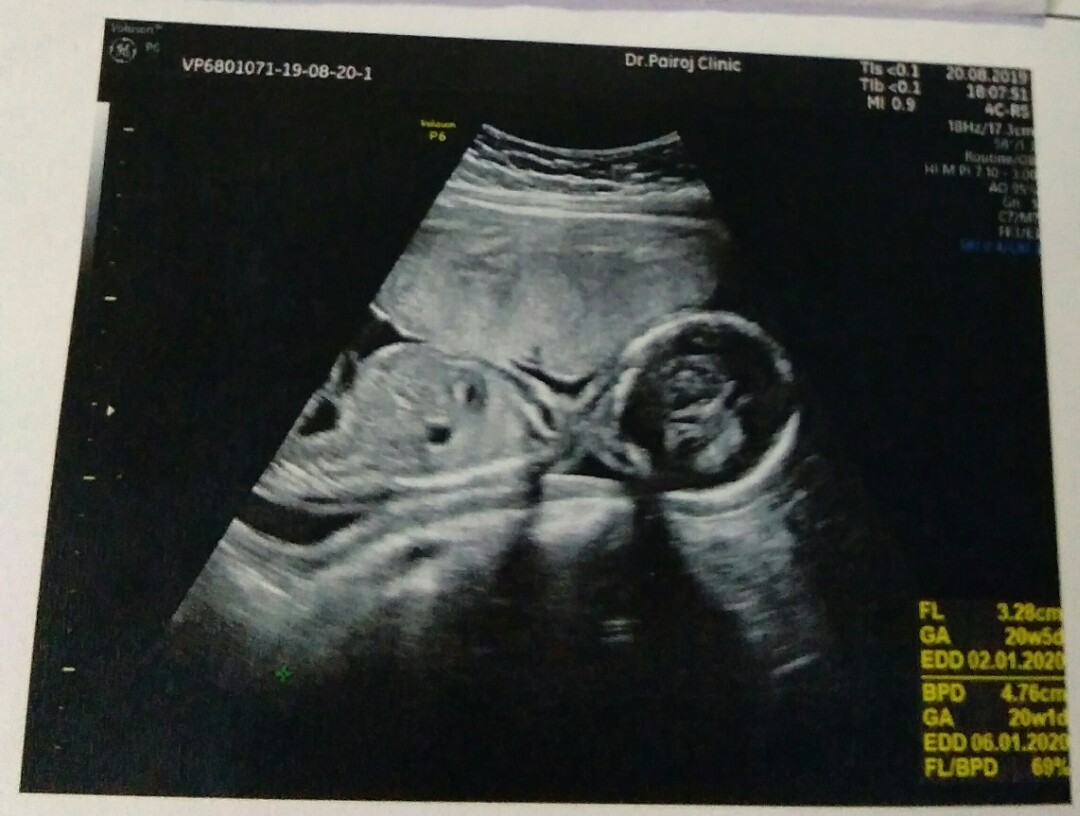

20สัปดาห์จ้ส

20สัปดาห์จ้า